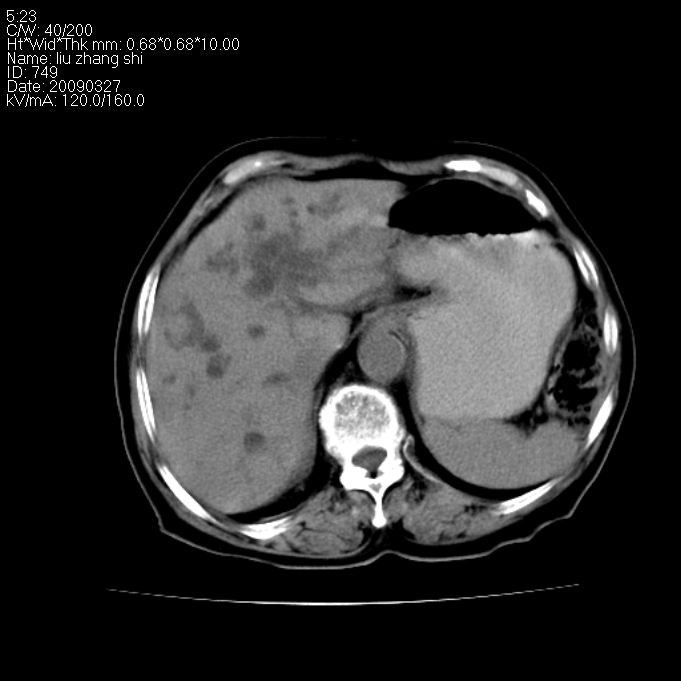

标题: CT19070:女 91岁 纳差 黄疸一月 [打印本页]

标题: CT19070:女 91岁 纳差 黄疸一月

胆囊明显增大,肝内胆管呈囊状及枯枝状扩张,肝右叶点状钙化灶:肝门部胆管癌可能.

1)胆系低位梗阻(肝内外胆管扩张,主胰管扩张,胆囊增大),原因待查;不排除壶腹癌所致可能。2)肝右叶后下段肝内胆管结石(或钙化)。

肝内胆管结石,肝总管肝内外胆管扩张,胆囊增大,胆总管胰头上部区占位【注意观察8,9两幅图像】--建议增强检查加mri 检查